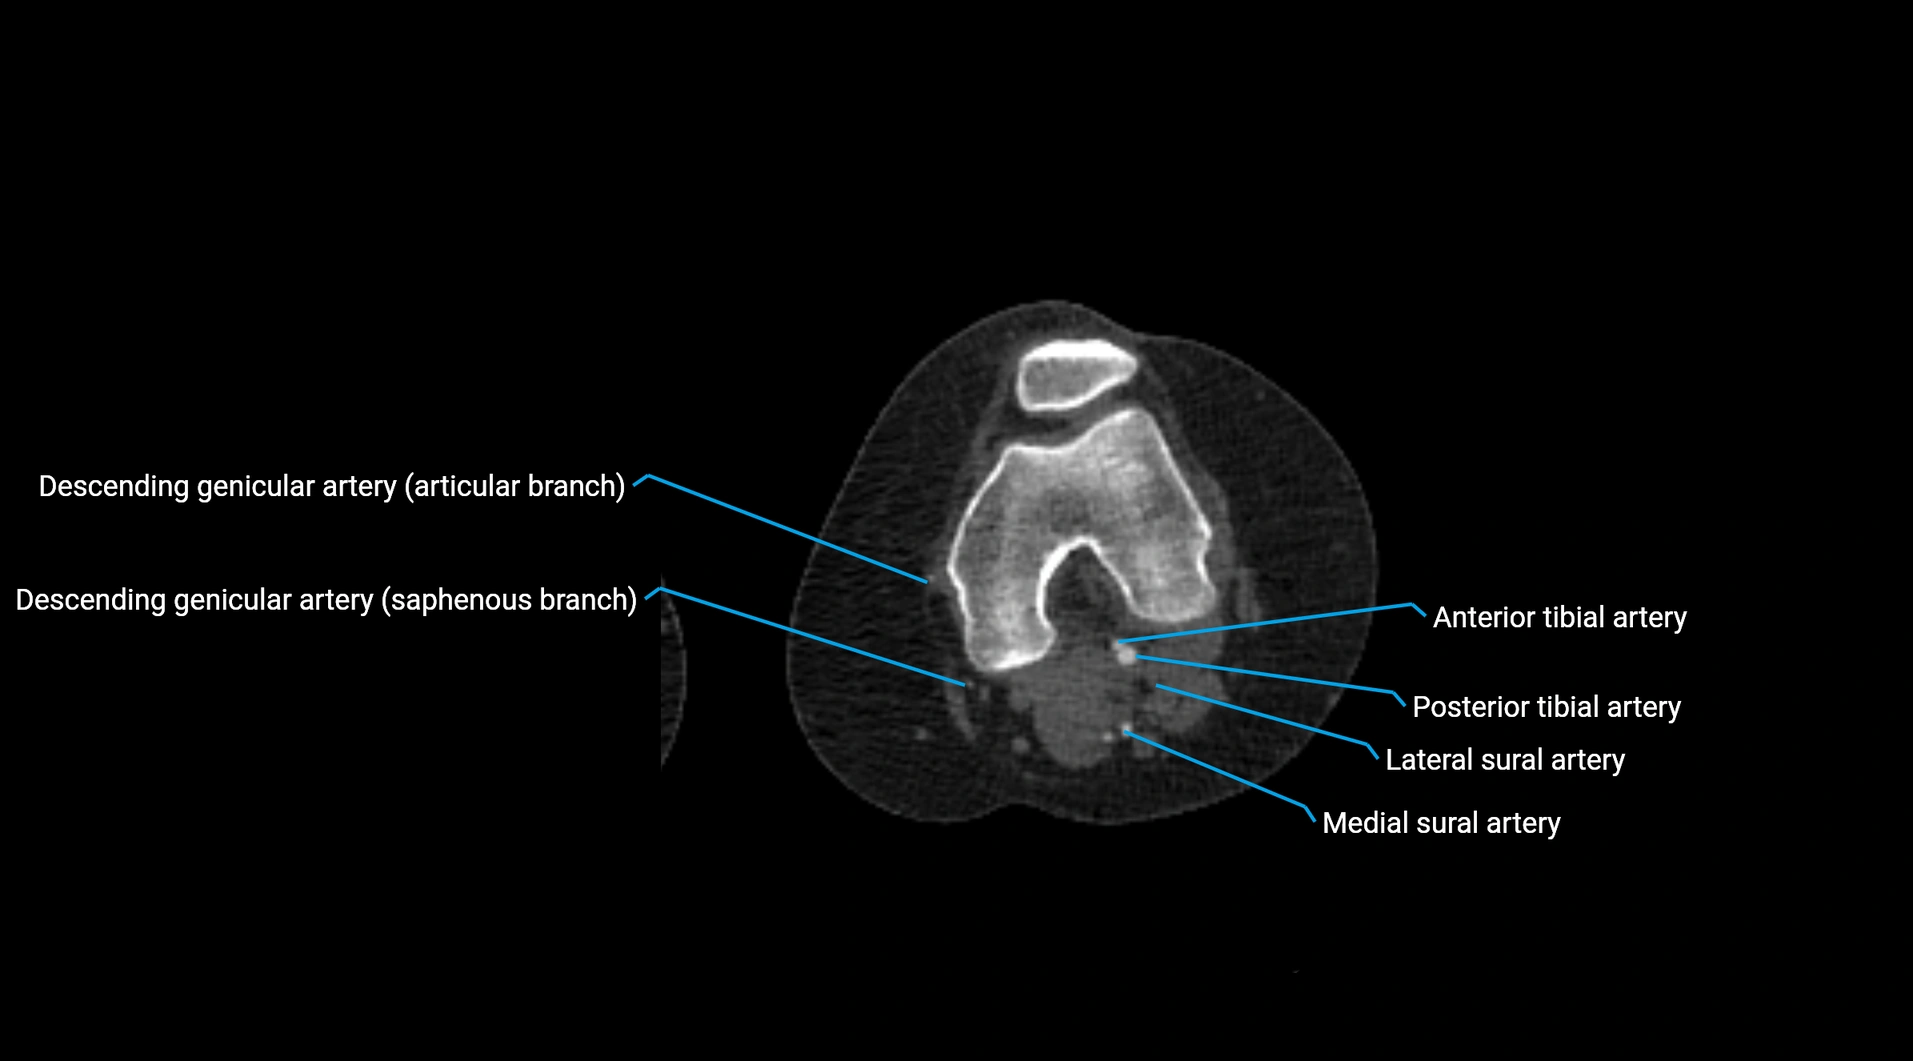

CT images

image